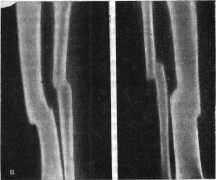

Рис. П. Открытый косой перелом в нижней трети правой голени, осложненный остеомиелитом (свищевая форма).

а - через 3 мес после травмы - положение отломков в гипсовой повязке после лечения; б - лечение аппаратом Илизарова; в - через 5 мес консолидация: состояние после снятия аппарата.